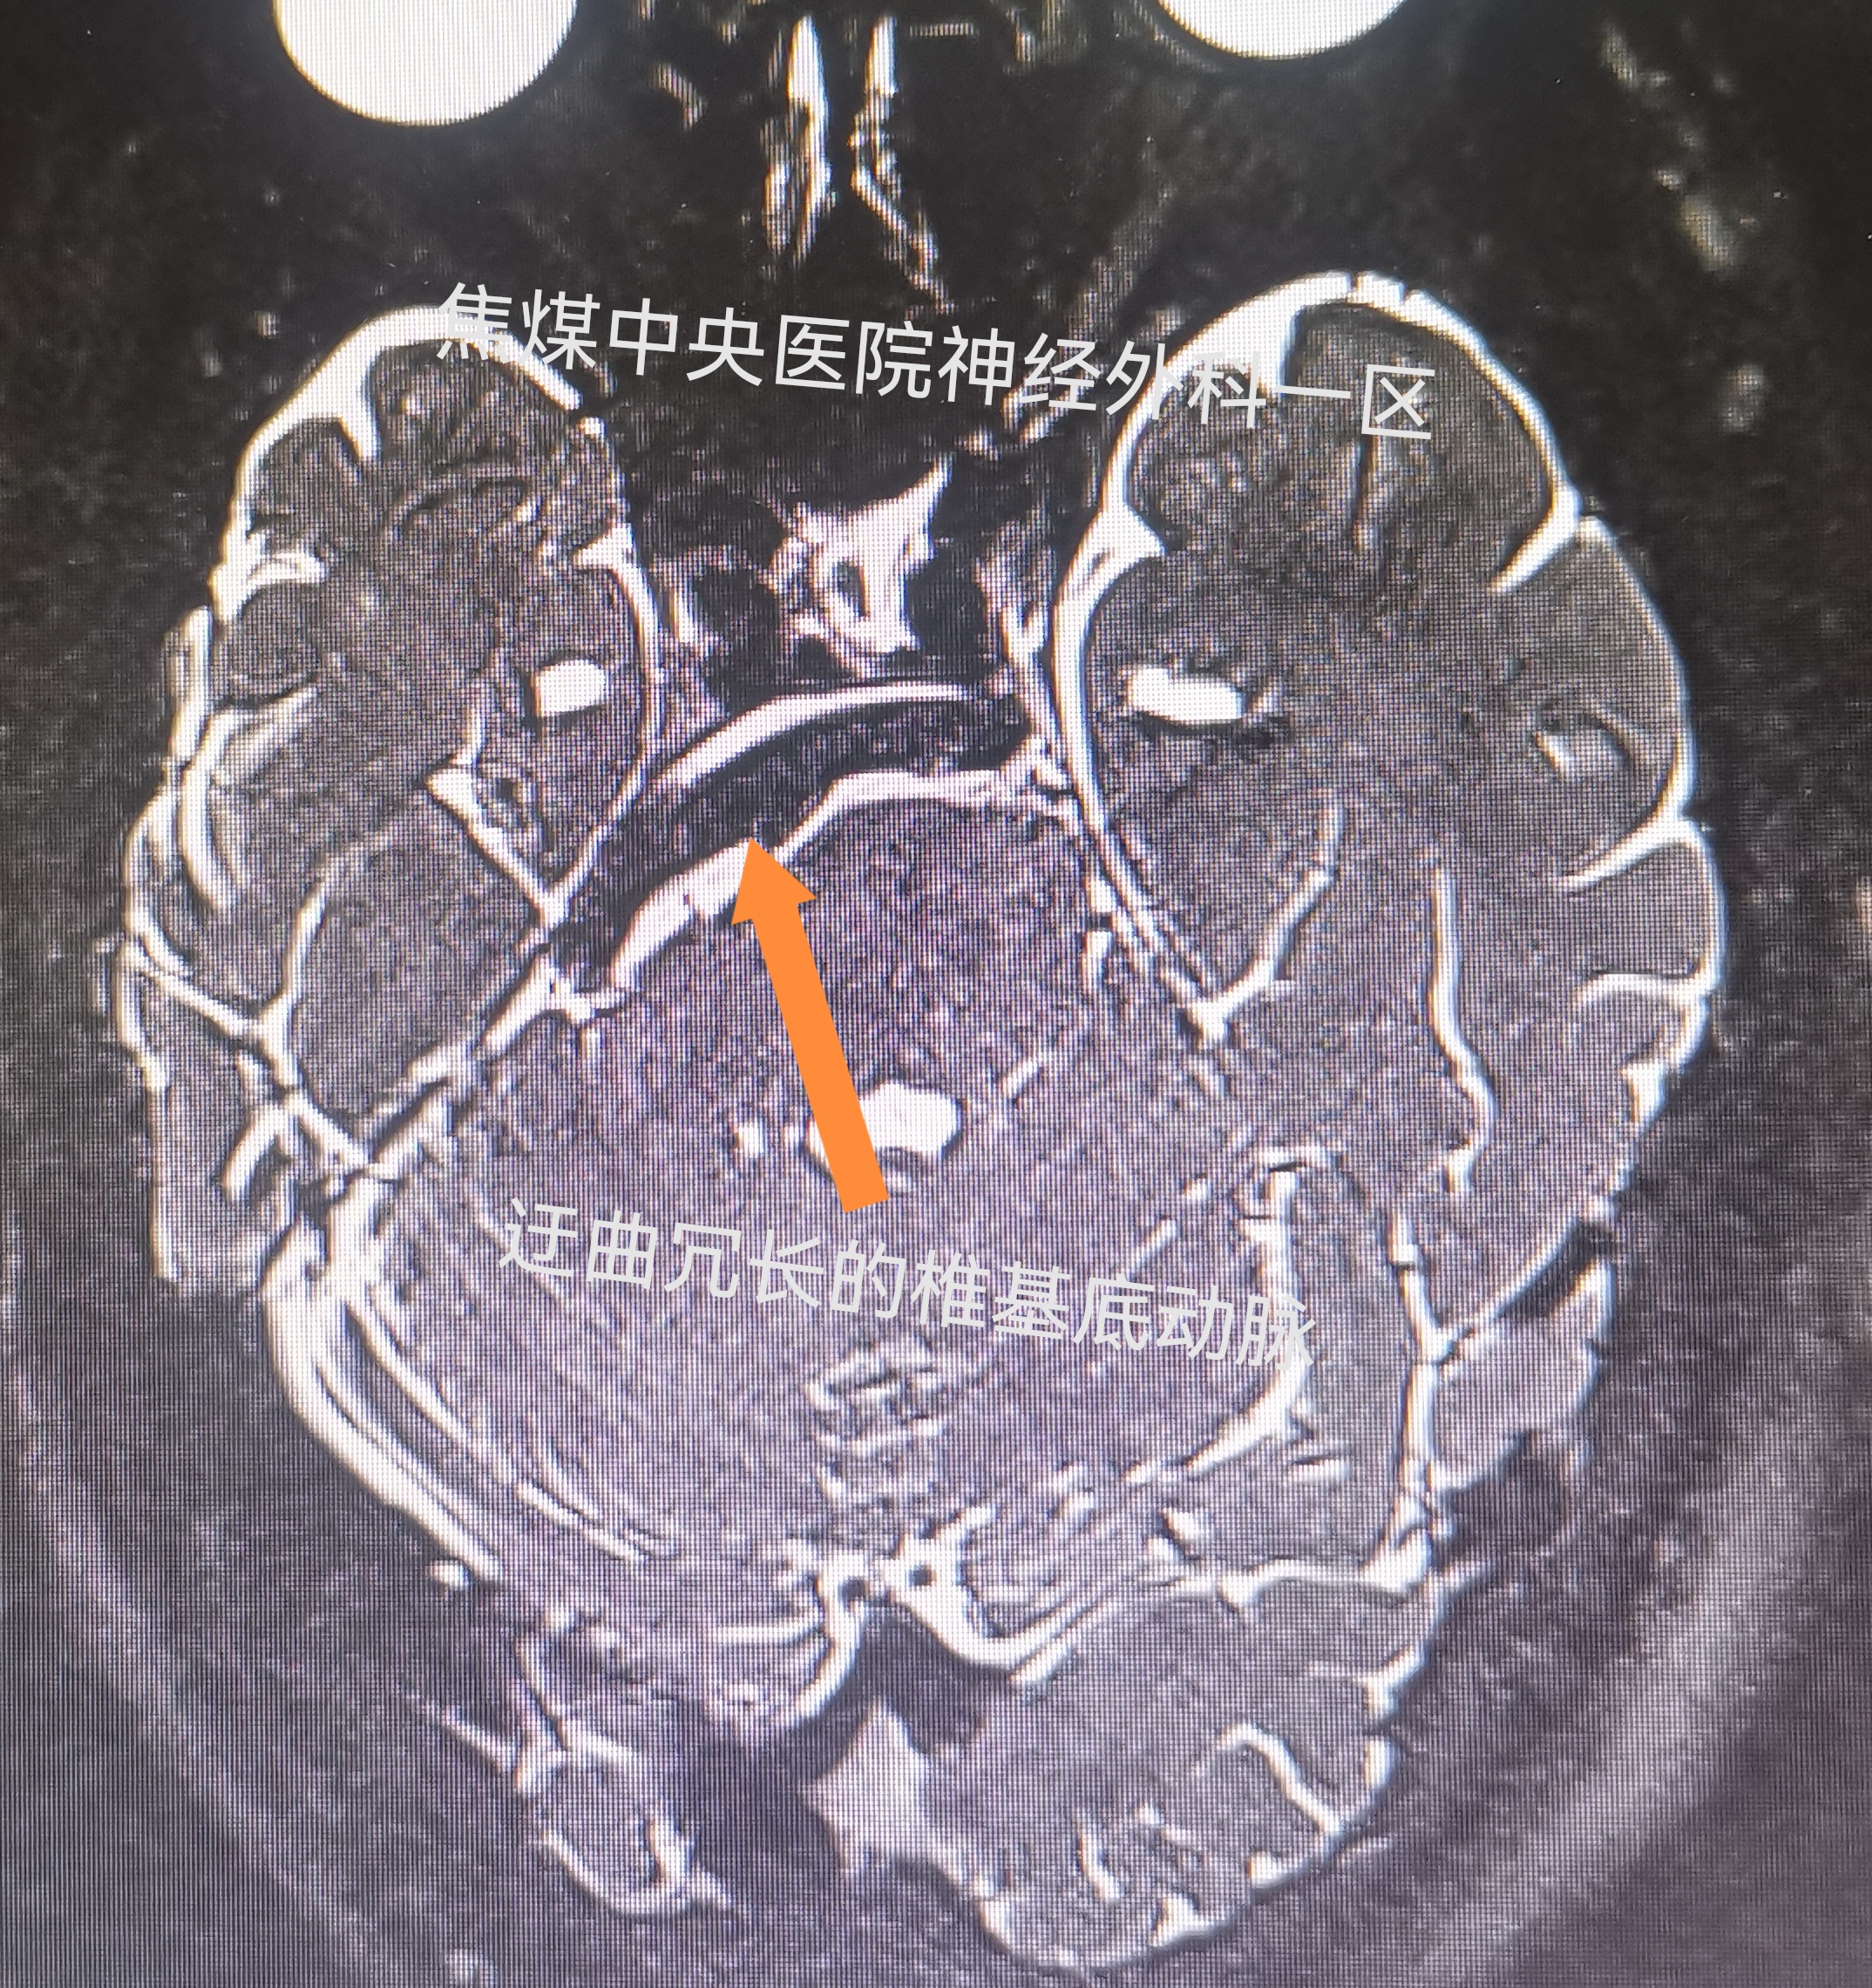

辅助检查:MRI示右侧椎动脉压迫三叉神经及面神经REZ区,且基底动脉达鞍上池

手术过程:插管全麻下,经右侧乙状窦后入路行右侧原发性三叉神经、面肌痉挛微血管减压手术,术中见迂曲冗长的右侧椎动脉压迫面神经出脑干部及三叉神经的CPA段,且将三叉神经挤压移位于天幕部,而此处的三叉神经呈薄片状,采用Teflon垫片将责任椎动脉推向颅底并用EC胶将该血管粘沾于颅底硬膜,查减压充分后关闭切口。

椎基底动脉迂曲冗长